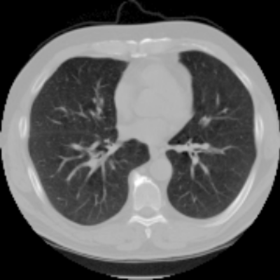

We then test our method on slices of chest CT images obtained from the Open Access Biomedical Image Search Engine [2]. Fig. 10(a) and 10(b) show the source image and target image respectively, and the intensity difference is shown in Fig. 10(c). The registration result obtained by our proposed method is shown in Fig. 10(d) (see also the result with the deformed underlying grid in Fig. 10(e)). From the final intensity difference plot in Fig. 10(f), it is easily to see that our method matches not only the two large components but also the small dot at the center very well. On the contrary, DDemons [47] produces a suboptimal registration result with a significantly larger mismatch of the small component at the center (see Fig. 10(g) and Fig. 10(h)).